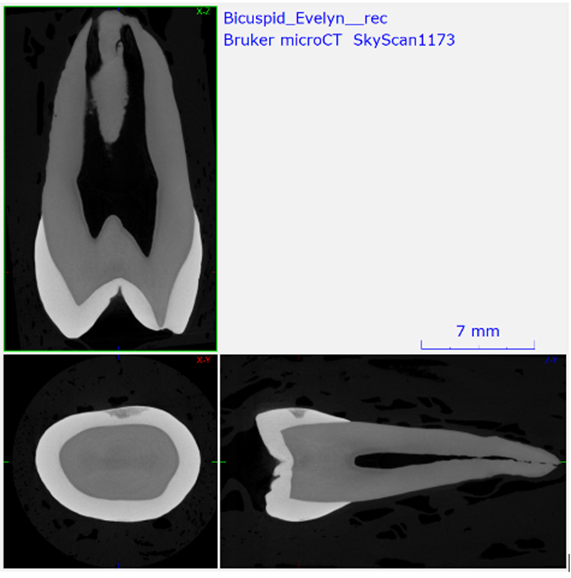

X-ray micro–computed tomography (micro-CT) addresses these limitations by enabling nondestructive, isotropic, three-dimensional imaging of intact dental specimens across a wide range of sizes and material compositions. Micro-CT datasets preserve spatial relationships between enamel, dentin, pulp spaces, restorative materials, and bone, allowing repeated segmentation and quantitative analysis without further specimen manipulation. Consequently, micro-CT now functions as a quantitative imaging backbone in endodontics, cariology, implantology, and dental materials science rather than a purely illustrative technique (Versiani et al., 2013).

A single micro-CT system, unlike clinical CT, can image large specimens like whole jaws at tens of microns and small regions at sub-micron scale.

Laboratory micro-CT systems generate three-dimensional datasets by acquiring hundreds to thousands of two-dimensional X-ray projection images as the specimen rotates relative to a fixed X-ray source and detector. For ex vivo dental specimens, this rotating-sample geometry maximizes geometric magnification and spatial resolution while maintaining mechanical simplicity. Projection images are reconstructed using cone-beam filtered back-projection or iterative algorithms to yield isotropic voxel volumes, enabling digital slicing in any plane without loss of resolution.

Unlike clinical CT, spatial resolution in micro-CT is not an intrinsic system constant. Achievable voxel size emerges from the coupled interaction between specimen size, source-to-object distance, object-to-detector distance, X-ray focal spot size, detector pixel pitch, and acquisition parameters such as exposure time and angular sampling (Hildebrand & Rüegsegger, 1997; Bouxsein et al., 2010). This scalability allows a single micro-CT platform to image whole jaws at tens of microns while also resolving dentin tubules or interfacial gaps at sub-micron scales.

For dental research, this flexibility is essential. Endodontic morphology requires sufficient resolution to resolve accessory canals and isthmuses without sacrificing field of view, while caries and demineralization studies demand high grayscale sensitivity and stable density calibration. Implant research often requires compromise between resolution and penetration to image both metal and bone within the same dataset. Micro-CT enables deliberate tuning of these tradeoffs, allowing researchers to design scans around the biological or materials question rather than forcing the question to fit the instrument (Faulwetter et al., 2013).

Root canal systems exhibit substantial anatomical variability, including bifurcations, accessory canals, apical deltas, and complex cross-sectional geometries. Micro-CT has become the reference standard for documenting this complexity because it preserves the intact three-dimensional network without interpretive bias from sectioning or projection overlap. Detailed morphometric analysis supports both anatomical classification and evaluation of instrumentation strategies.